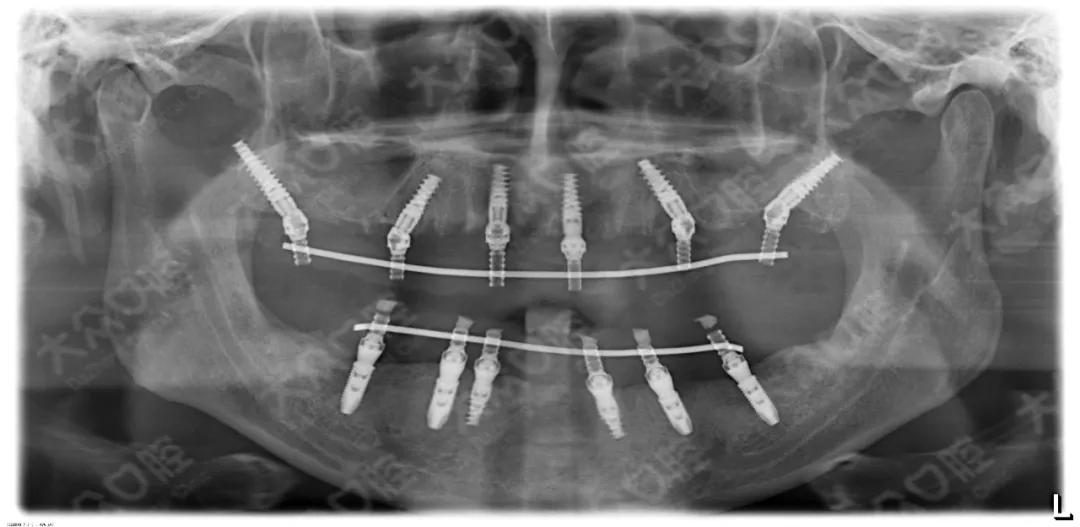

大众口腔成功开展高难度穿翼板viiv即刻种植即刻修复手术!

大众口腔成功开展高难度穿翼板viiv即刻种植即刻修复手术

北京中诺口腔上颌穿翼板全口种植病例

重庆泰康拜博口腔穿翼板种植

线下公益课翼板种植极度萎缩上颌即刻负重方案

上海鼎植口腔高振华穿颧穿翼种植为无牙颌患者种一口好牙